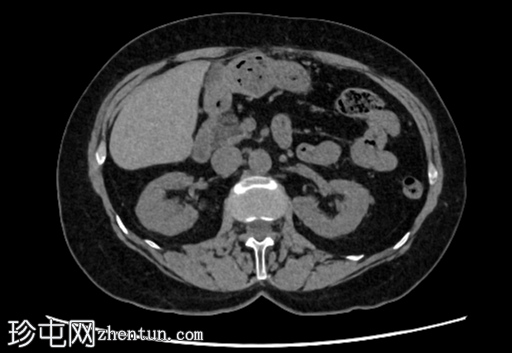

轴位

平扫

右肾后上极可见2.8 cm外生性强化病灶,提示肾细胞癌(RCC)。右肾静脉和下腔静脉通畅。未见明显局部淋巴结肿大。右肝叶可见高密度金属影。可见含脂肪的脐疝。